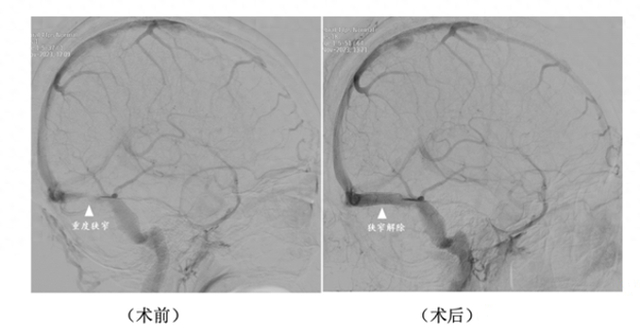

在血管内微创治疗手术中,仁济医院神经外科副主任医师赵兵准确判断了吴女士静脉窦狭窄病变的位置,精准测量了静脉窦狭窄的压力差,最终证实静脉窦狭窄是导致吴女士痛苦的根源。

随即,医生团队为吴女士实施了静脉窦支架成形手术。手术非常成功,吴女士在全麻后苏醒过来,脸上露出了久违的笑容,头痛和头胀的症状也明显得到缓解,看东西变得更加清晰了,左手的麻木无力感也完全消失了。

潘耀华表示,目前,脑血管造影是诊断该疾病的“金标准”,能够同时测定静脉窦狭窄两端的压力差,有助于准确做出诊断,并且精准指导治疗和判断预后。对于严重狭窄并且狭窄两端存在明显压力差的患者,血管内微创重建静脉窦是一种安全可行的治疗方法。